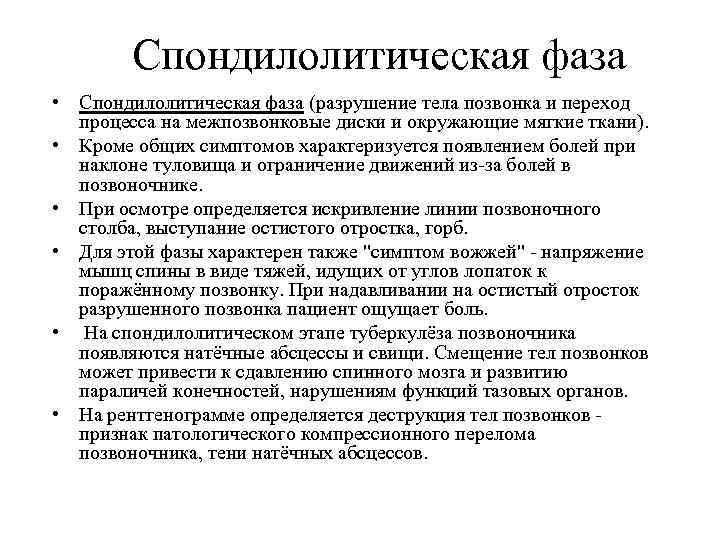

Спондилолитическая фаза • Спондилолитическая фаза (разрушение тела позвонка и переход процесса на межпозвонковые диски и окружающие мягкие ткани). • Кроме общих симптомов характеризуется появлением болей при наклоне туловища и ограничение движений из-за болей в позвоночнике. • При осмотре определяется искривление линии позвоночного столба, выступание остистого отростка, горб. • Для этой фазы характерен также "симптом вожжей" - напряжение мышц спины в виде тяжей, идущих от углов лопаток к поражённому позвонку. При надавливании на остистый отросток разрушенного позвонка пациент ощущает боль. • На спондилолитическом этапе туберкулёза позвоночника появляются натёчные абсцессы и свищи. Смещение тел позвонков может привести к сдавлению спинного мозга и развитию параличей конечностей, нарушениям функций тазовых органов. • На рентгенограмме определяется деструкция тел позвонков - признак патологического компрессионного перелома позвоночника, тени натёчных абсцессов.

Спондилолитическая фаза • Спондилолитическая фаза (разрушение тела позвонка и переход процесса на межпозвонковые диски и окружающие мягкие ткани). • Кроме общих симптомов характеризуется появлением болей при наклоне туловища и ограничение движений из-за болей в позвоночнике. • При осмотре определяется искривление линии позвоночного столба, выступание остистого отростка, горб. • Для этой фазы характерен также "симптом вожжей" - напряжение мышц спины в виде тяжей, идущих от углов лопаток к поражённому позвонку. При надавливании на остистый отросток разрушенного позвонка пациент ощущает боль. • На спондилолитическом этапе туберкулёза позвоночника появляются натёчные абсцессы и свищи. Смещение тел позвонков может привести к сдавлению спинного мозга и развитию параличей конечностей, нарушениям функций тазовых органов. • На рентгенограмме определяется деструкция тел позвонков - признак патологического компрессионного перелома позвоночника, тени натёчных абсцессов.